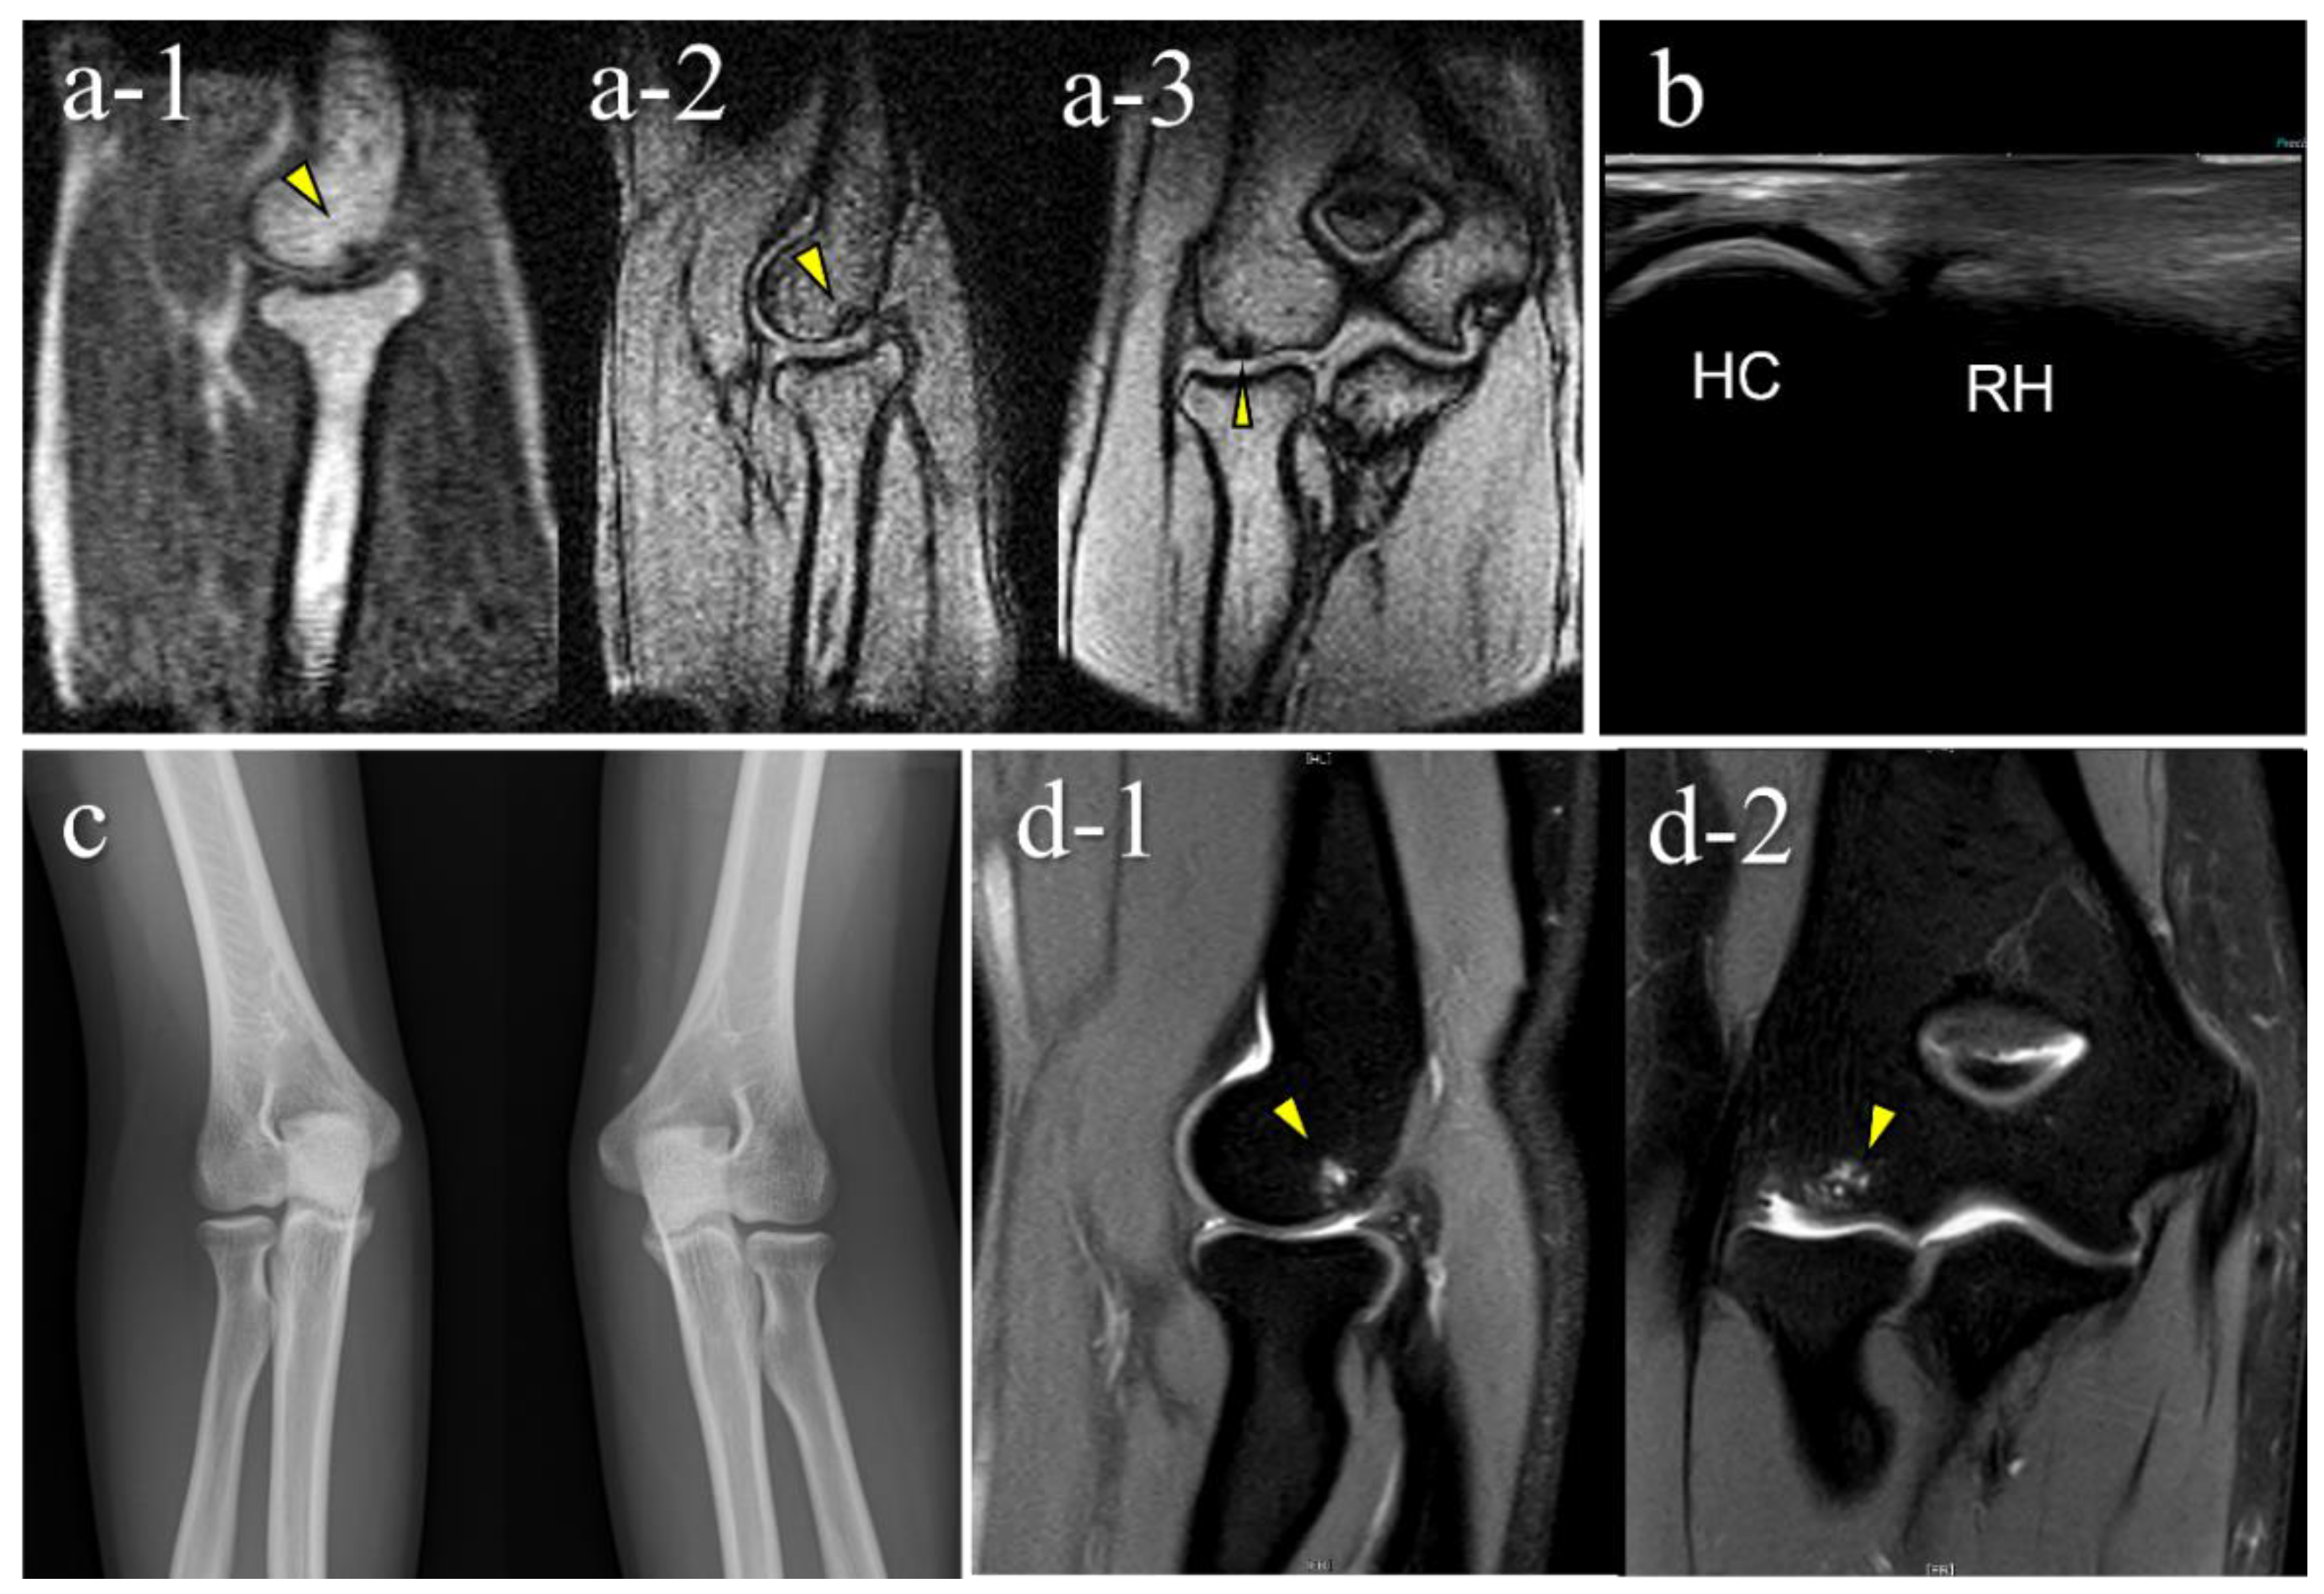

| 1 | 12 | M | - | − (1st) | + (B) | OCD | II | lateral | 15 |

| 2 | 11 | M | + | + (1st) | + (B) | OCD | I | central | 10 |

| 3 | 12 | M | - | + (2nd) | + (B) | OCD | II | central | 9 |

| 4 | 12 | M | + | + (2nd) | + (B) | OCD | II | lateral | 11 |

| 5 | 12 | M | + | + (2nd) | − (B) | OCD | I | central | 3.5 |

| 6 | 15 | F | - | + (2nd) | − (C) | not OCD | posterior | 3.5 | |

| 7 | 12 | M | - | + (2nd) | − (D) | OCD | I | central | 5.5 |